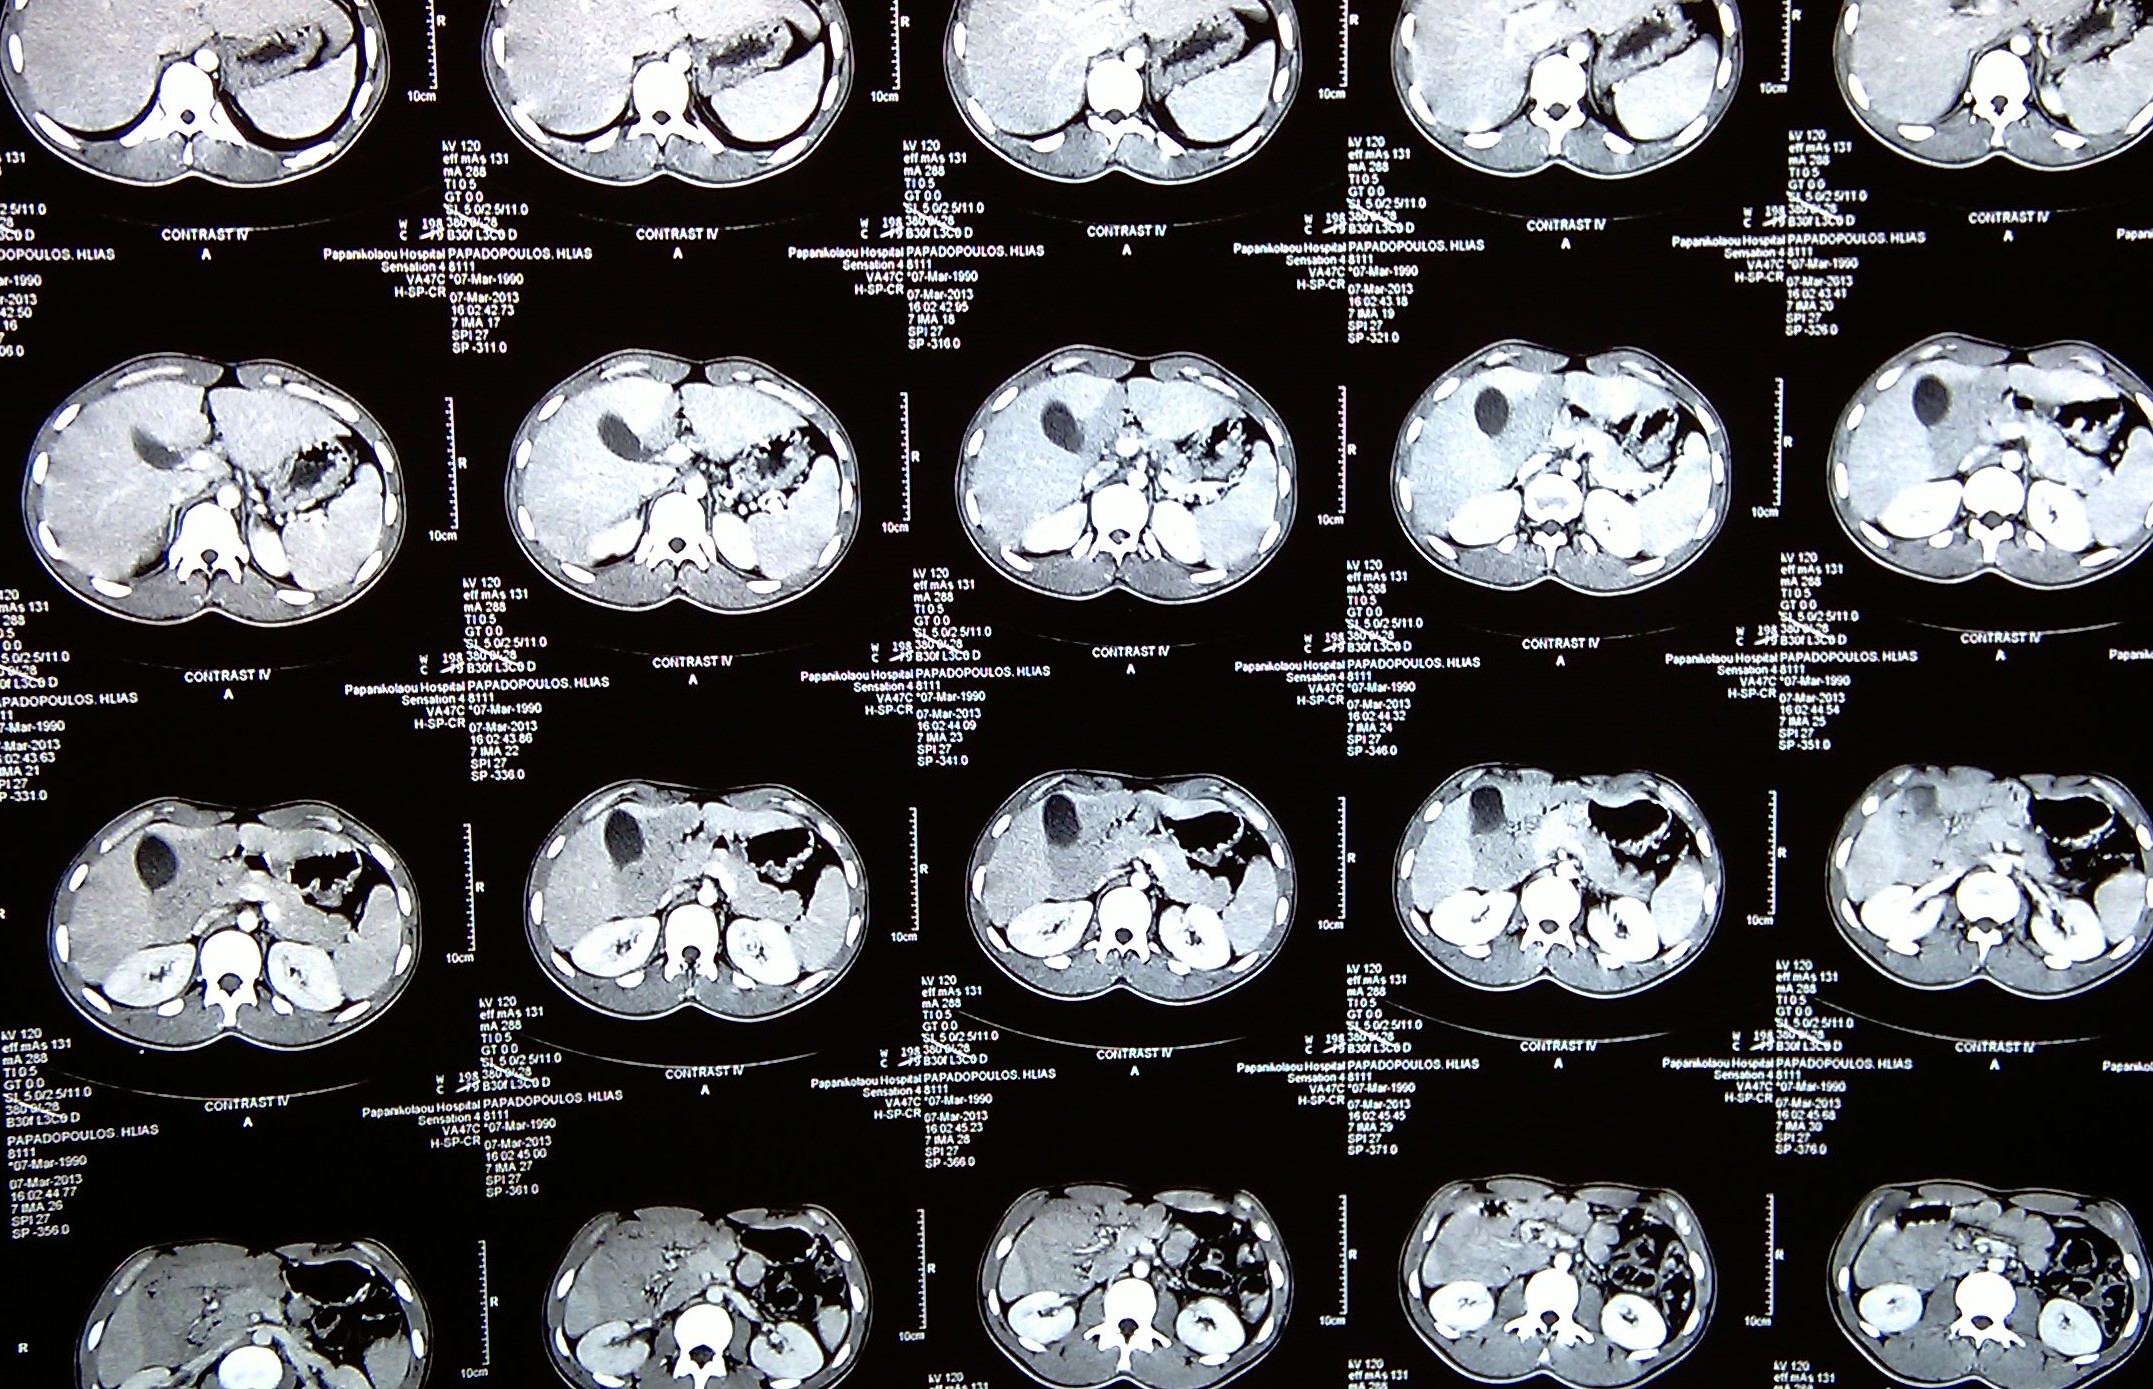

CT κοιλίας με σκιαγραφικό που αναδεικνύει το λεπτό έντερο στο κέντρο της κοιλίας εντός παχέος ινώδους υμένα (Ευγενική παραχώρηση Dr. V. Penopoulos)